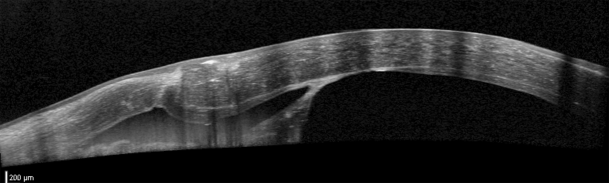

Fig. 2

a Anterior segment optical coherence tomography of case 1 showing the site of Descemet’s membrane perforation. b Lamellar dissection was performed to the level of pre-descemetic stromal layers in the center and more anterior in the perforation area

Anterior segment optical coherence tomography (AS-OCT, SS-1000 Casia; Tomey Corporation, Nagoya, Japan, and Spectralis HRA2; Heidelberg Engineering, Heidelberg, Germany) confirmed the dissection plane to be just anterior to DM (recipient stromal thickness 36 µm) except in the perforation area, where some deep stromal tissue had been left in place (recipient stromal thickness 124 µm; Fig. 2). The cornea was clear and no edema was noted in the area of the DM tear. Endothelial cell density (ECD) of the central cornea assessed using in vivo confocal microscopy (IVCM, Heidelberg Retina Tomographer II with Rostock Cornea Module; Heidelberg Engineering, Heidelberg, Germany) 3 months after surgery was 2,706 ± 22 cells/mm2 at a focal depth of 496 µm with some polymegathism.